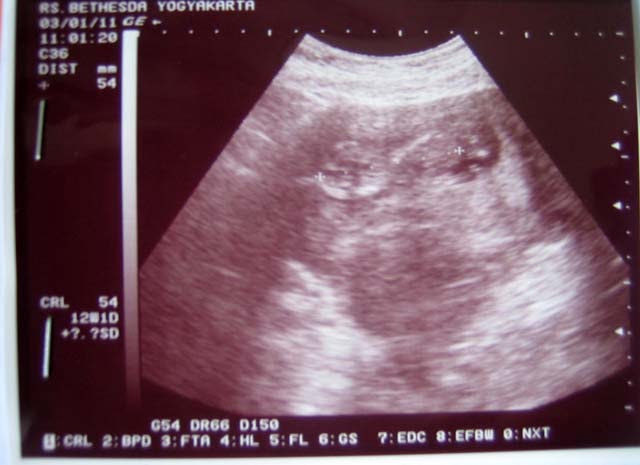

Hamil 11 Minggu Perut Kedutan / 50 Fakta Kehamilan (BAGIAN 3) - Tips Cepat Hamil, Dokter ... : Usia hamil 11 minggu, wajah, organ reproduksi, hingga folikel rambut bayi mulai terbentuk dan berkembang.

Hamil 11 Minggu Perut Kedutan / 50 Fakta Kehamilan (BAGIAN 3) - Tips Cepat Hamil, Dokter ... : Usia hamil 11 minggu, wajah, organ reproduksi, hingga folikel rambut bayi mulai terbentuk dan berkembang.. Apa yang terjadi pada saat hamil 10 11 dan 12 minggu? Kumpulan arti kedutan perut saat hamil lengkap dengan tafsir dan pertandanya menurut para ahli, psikologi, dalam islam dan menurut primbon. Sakit perut saat hamil merupakan keluhan yang sering dialami ibu hamil. Selain parasnya yang cantik dan rupawan, setiap gaya busana yang. Beberapa di antaranya normal, tapi ada juga yang harus diwaspadai.